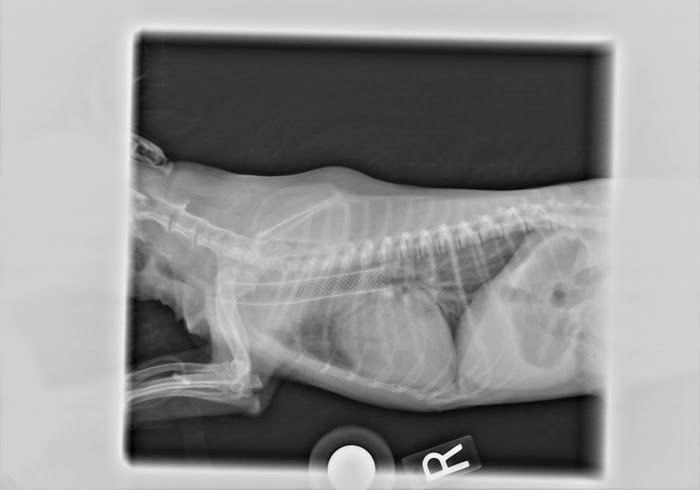

Chest and neck x-rays of dog with collaping trachea

The trachea is the main airway that delivers air from the oral cavity into the lungs when the chest cavity expands to breathe.  There are two portions of the trachea: the extrathoracic trachea in the neck, and the intrathoracic trachea inside the chest.  As it courses into the chest cavity the trachea then splits into two primary bronchi that bring air directly to each individual lung, respectively.  Collapsing trachea results when the cartilaginous rings of the trachea lose their structural integrity and partially collapse during inhalation.  Depending on the severity of the tracheal collapse, this can create a choking sensation for the dog, or progress to near asphyxiation.